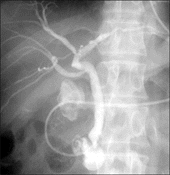

胆嚢結石による黄疸

充満胆石による胆管狭窄で黄疸出現.ENBDで黄疸を改善してから,胆嚢結石はラパコレで摘除.

ENBD